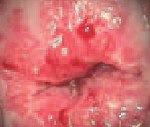

Дифференцировать простую и атипичную форму заболевания возможно только после гистологического изучения биоптата. Пациенток с эритроплакией могут беспокоить клейкие выделения желтоватого цвета. При кольпоскопии выявляются темно-красные участки с неровными границами, приподнятые над неизмененной слизистой.

При визуальном осмотре влагалищной порции шейки матки с помощью зеркал гинеколог оценивает форму наружного зева, окраску слизистой, характер секрета, видимые патологические процессы. В рамках гинекологического осмотра производится забор мазков с поверхности шейки матки для онкоцитологического исследования (ПАП-тест). При выявлении подозрительных участков шейки матки следующим этапом выполняется простая кольпоскопия, при необходимости - расширенное исследование с проведением медикаментозных проб (пробы Шиллера и тд ). Каждой форме фоновых и предраковых заболеваний шейки матки соответствует своя кольпоскопическая картина, поэтому на данном этапе возможна дифференциальная диагностика патологий. Для выявления изменений эндоцервикса используется цервикоскопия.